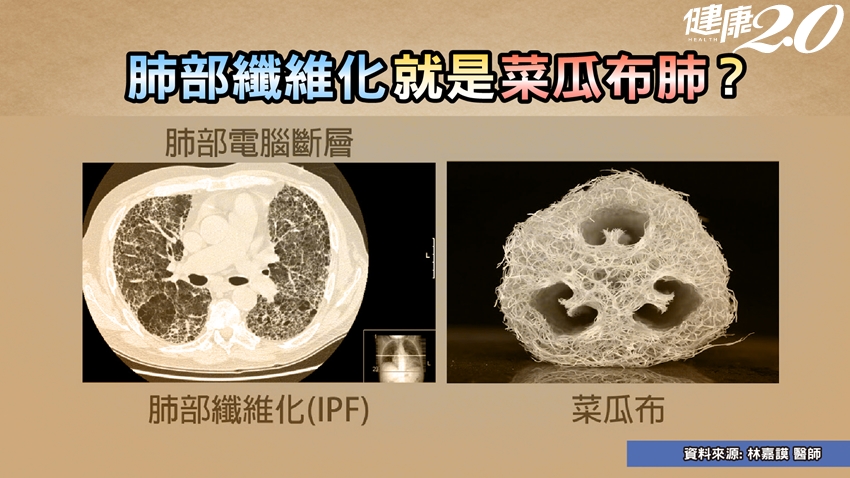

菜瓜布肺 死亡率高達5成

特發性肺纖維化(IPF)俗稱「菜瓜布肺」,是最常見且最致命的間質性肺病,死亡率高達5成,甚至比肺癌還要高。但臨床上,可以用於治療IPF的藥物選擇稀少,治療效果不明確,預後也很差,往往需要進行心肺移植,才能存活。

延伸閱讀:「菜瓜布肺」常被誤診,比癌症可怕